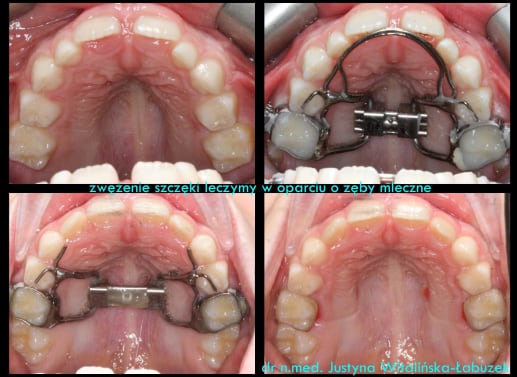

3. LEKARZ DENTYSTA – jego zadaniem jest ekspansja zwężonych kości szczęk. Anatomia człowieka jest taka, że zęby górne tkwią w dwóch, parzystych kościach szczęk. Te same kości budują dno jamy nosowej, dlatego współpraca lekarzy laryngologa oraz dentysty powinna być tak ścisła. Rozbudowa dolnego piętra (szczęki) sprawia, że poszerza się także górne piętro (nos) i dziecku oddycha się lepiej.